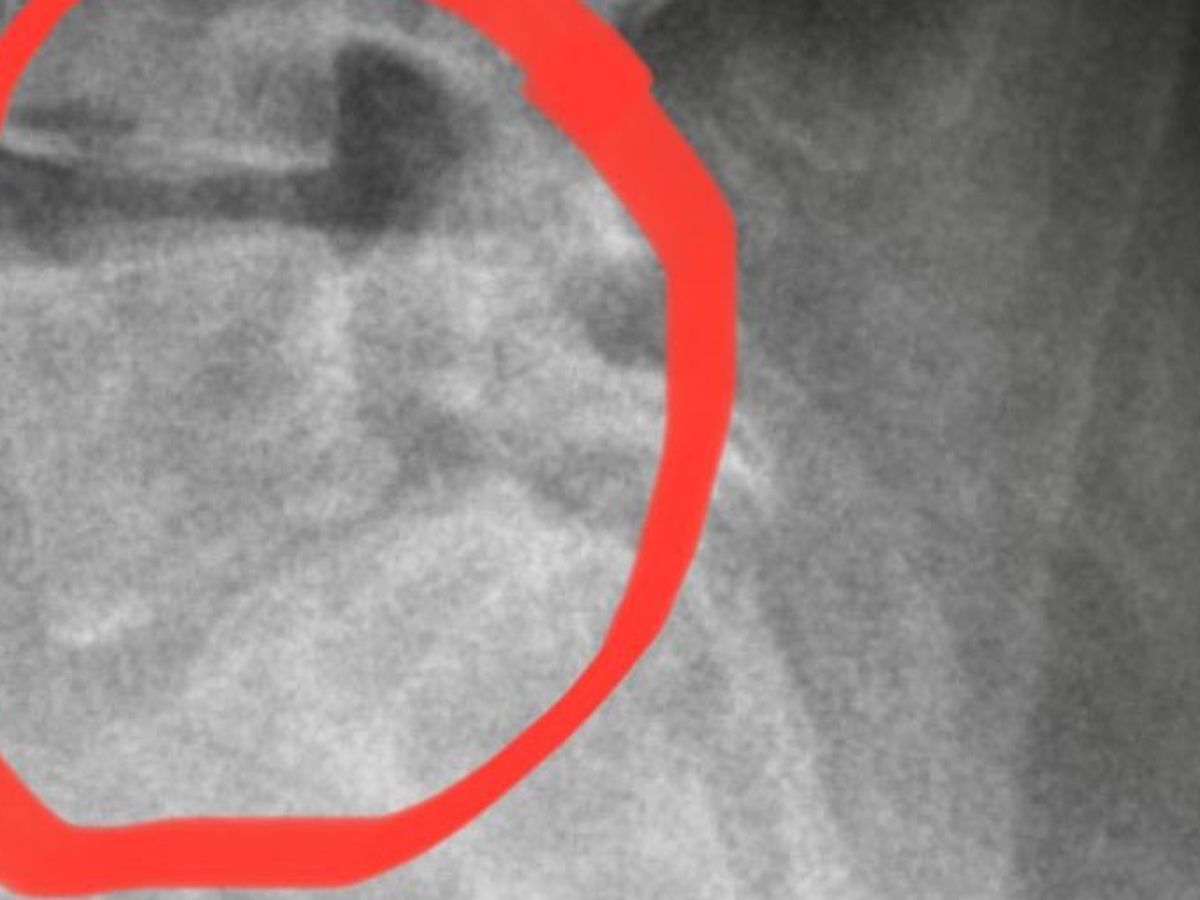

My name is Letty and I have a condition called Spondylolisthesis is a spinal condition that causes lower back pain. It occurs when one of our vertebrae slips out of place onto the vertebra below it. In this condition, a stress fracture on the pars articularis (small, thin portion of the vertebra that connects the upper and lower joints on the spine.) causes the vertebrae to slip forward on the vertebrae directly below it.

I had a tumor on my back which was operated on in 2016. As a consequence my back needed to be fused from L1 to L3. The situation is that the titanium bars that they had to put on were straight when they needed to be curved. Due to the unnatural position the rest of my back was forced to move to compensate for this and thus the listhesis at L5 started and as time progressed it has been getting worse.

The ONLY solution was to have another operation to remove the bars from the first operation, reposition the vertebrae and fuse all the way from L1 to S1 with curved bars and a lumbar box separator. Due to my doctor advising me of the urgency from my deterioration, I have had the surgery on the 19th September.